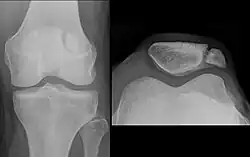

The patella (pl.: patellae or patellas), also known as the kneecap, is a flat, rounded triangular bone which articulates with the femur (thigh bone) and covers and protects the anterior articular surface of the knee joint. The patella is found in many tetrapods, such as mice, cats, birds, and dogs, but not in whales, or most reptiles.

The patella is a sesamoid bone roughly triangular in shape, with the apex of the patella facing downwards. The apex is the most inferior (lowest) part of the patella. It is pointed in shape, and gives attachment to the patellar ligament.

The upper three-quarters of the patella articulates with the femur and is subdivided into a medial and a lateral facet by a vertical ledge which varies in shape.

In the adult the articular surface is about 12 cm2 (2 sq in) and covered by cartilage, which can reach a maximal thickness of 6 mm (1⁄4 in) in the centre at about 30 years of age. Owing to the great stress on the patellofemoral joint during resisted knee flexion, the articular cartilage of the patella is among the thickest in the human body.